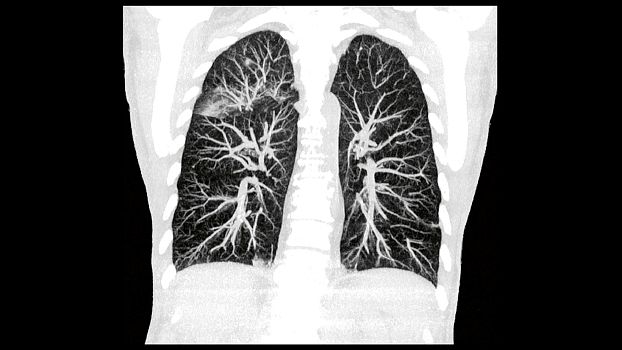

SOMATOM go.Up позволяет проводить скрининговые исследования лёгких и толстой кишки, а также исследования сердца для оценки коронарного кальция. Благодаря субмиллиметровой коллимации SOMATOM go.Up обеспечивает высокое пространственное разрешение, тем самым повышая чувствительность диагностики в онкологии.